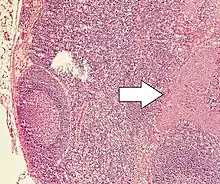

Micrograph of a neuroendocrine tumor. H&E stain.

Neuroendocrine tumors (NETs) are neoplasms that arise from cells of the endocrine (hormonal) and nervous systems. They most commonly occur in the intestine, where they are often called carcinoid tumors, but they are also found in the pancreas, lung, and the rest of the body.